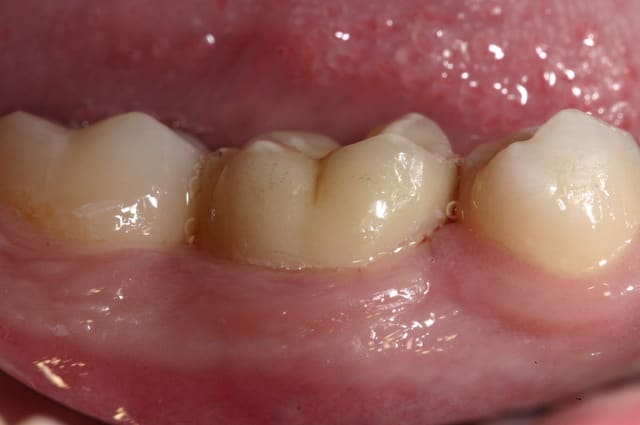

Je privilégie la céramique, toujours.

@ Steph : Sur un délabrement tel que celui de la photo présentée, on peut envisager que la tendreté de l'onlay composite amortit et absorbe les forces et préserve ce qu'il reste de cette molaire alors que ce ne sera pas le cas avec l'onlay céramique.

je ferais plutot une V-prep en vitrocéramique Vita par exemple, c'est la plus souple et la plus facile à coller.

L'onlay répartit mieux les forces occlusales, et quand il s'agit d'onlay la céramique est recommandée.

Ici c'est de l'e-max.

tres joli boulot....

Merci hall, mais là j'y suis pas pour grand-chose ; faut avoir un prothésiste qui maîtrise la céram.

On dirait des vraies...